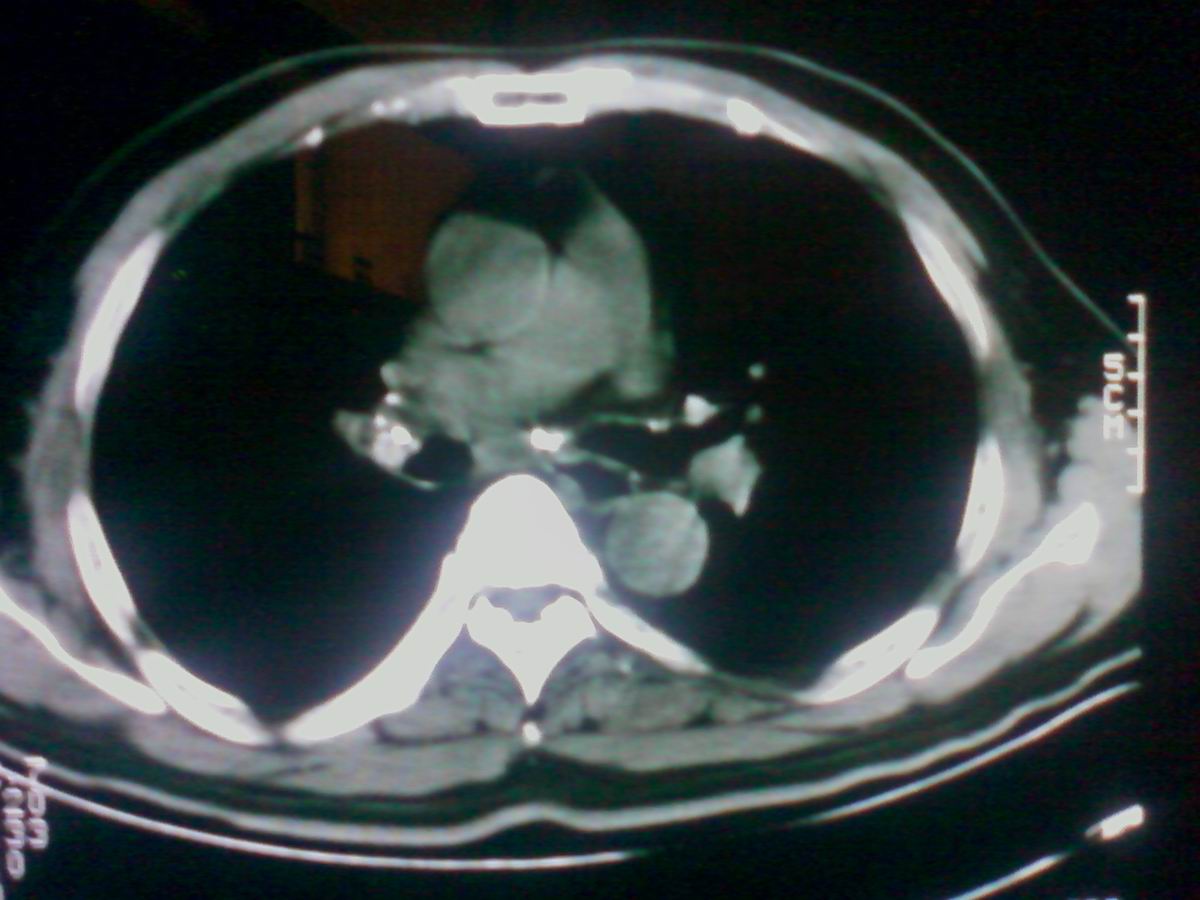

气管后部见半圆形软组织密度病灶,考虑占位,建议气管镜除外鳞癌。

气管上段的肿瘤多为良性乳头状瘤,气管下段的肿瘤多为鳞癌,气管中段的良恶性各占一半。本例位于气管下段,先按恶性处理。不过纤支镜是免不了的。